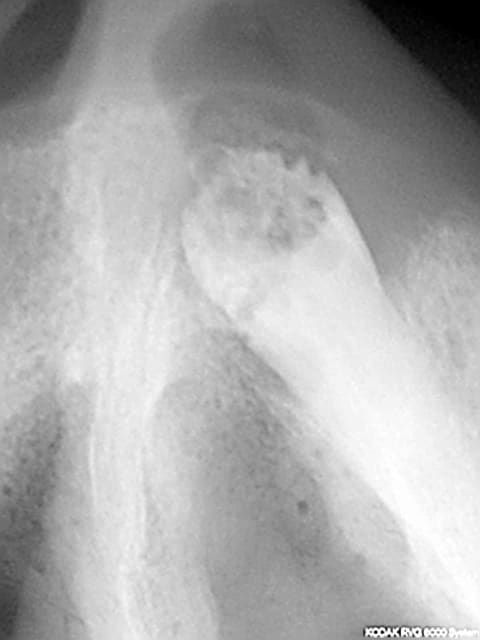

passage à l'acte la semaine dernière

EII sur 11 natea 4.1*12

natea 3.6*12 en 21

ostim + prf

à suivre...

03685 x 00000126 3 tzvgz0 - Eugenol

3f3boxni50k58rq7e9ce9ddqrxgk - Eugenol

fouilla on voit tes doigts sur la radio.